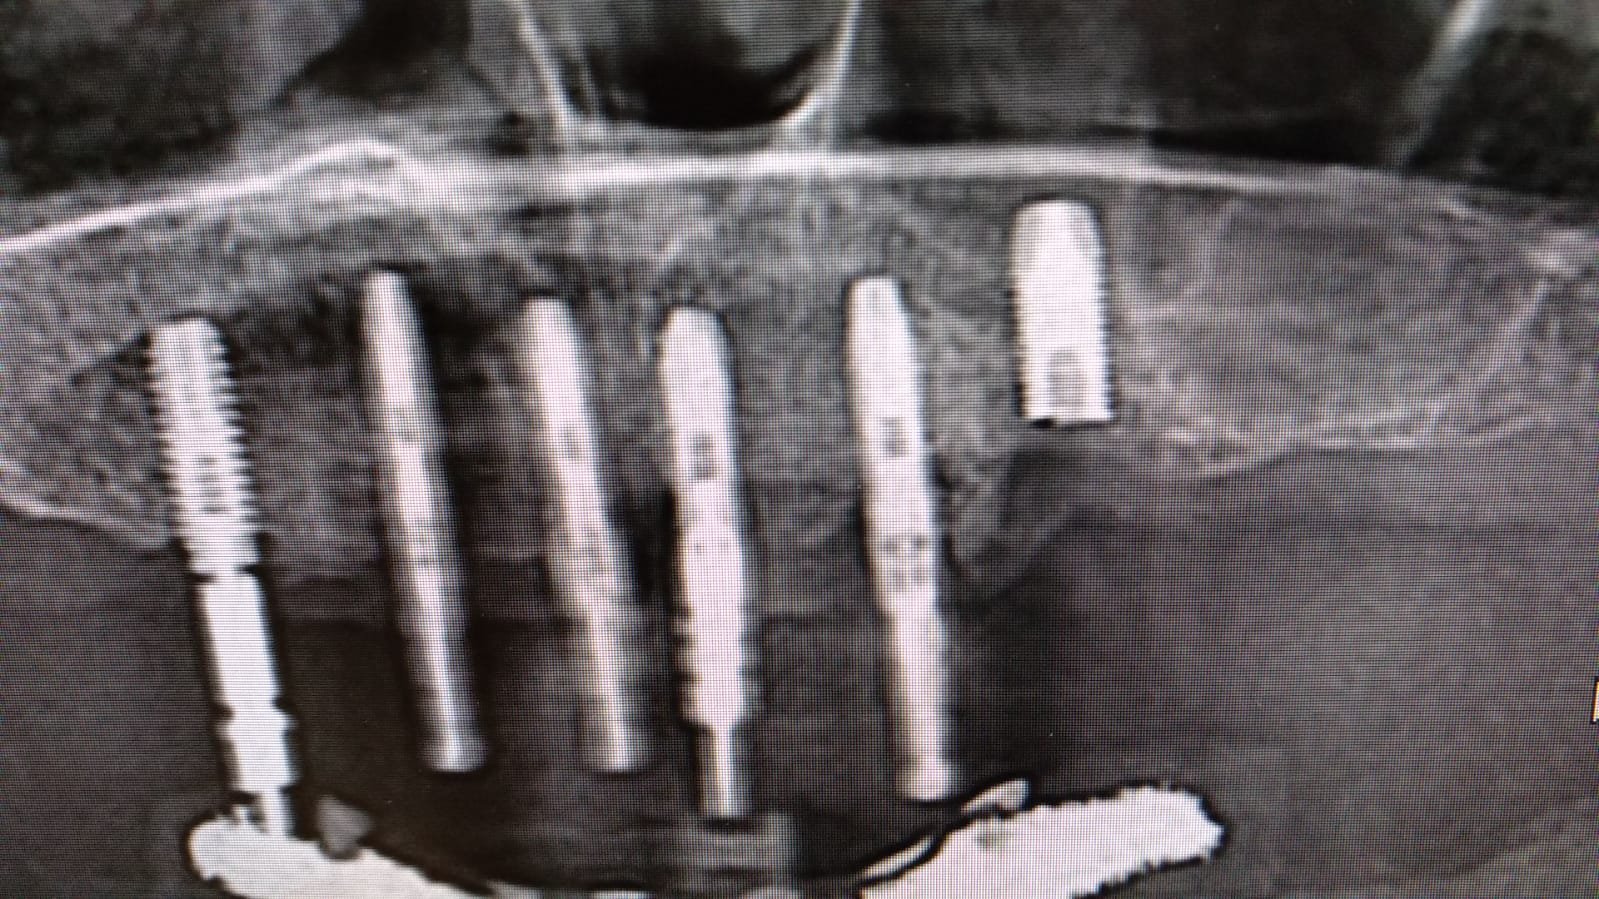

Buenas tardes compañeros. Nos envían este caso de los compañeros de LUSOBIONIC ESPAÑA a ver si les podemos echar un cable y averiguar qué implantes son. Gracias!

Implantes de conexión externa cuya marca desconozco. Necesito los superiores para terminar de rehabilitar el caso. Muchas gracias

Son implantes de conexión externa, y necesito saber qué tipo de pilares corresponde a estos implantes, gracias